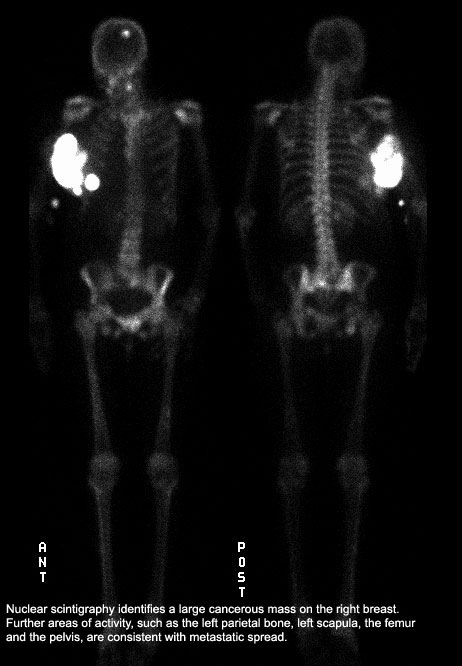

A 58-year-old woman presents to her physician complaining of rib and back pain following a trip-and-fall accident. She was concerned that she may have broken something. On physical exam, the physician notes some rib tenderness, but also finds a palpable mass in her right breast. The woman says that she does not perform monthly self-exams on her breasts and has not had a breast exam since her last checkup several years ago. A mammogram and rib and spine films were ordered by the physician. The mammogram shows a large mass consistent with cancer in her right breast and the bone films show multiple osseous lesions consistent with metastatic disease.

The prognosis would depend upon the extent of the metastases and which organs were involved. This could be assessed by CT scans, nuclear scintigraphy, liver, brain and bone scans, to identify tumors or areas of rapidly dividing cells indicative of cancer metastases.